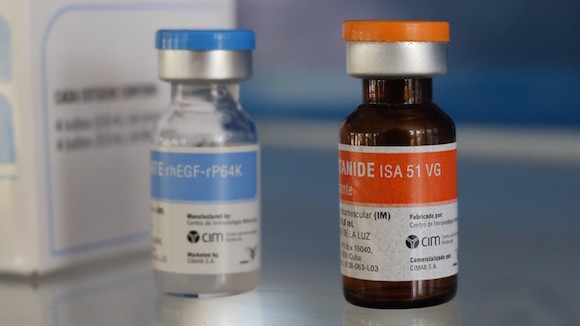

Se llama CIMAVAX, y mientras el CIM la llama vacuna, es importante tener en cuenta que el medicamento no previene la enfermedad como una vacuna tradicional, al menos en su forma actual. En cambio, mantiene los tumores diagnosticados controlados mediante la inhibición de su crecimiento, actuando como un tratamiento. Esto se conoce como una vacuna terapéutica.

En lugar de dirigirse a las células cancerosas directamente, la vacuna actúa como una forma de inmunoterapia, aprovechando el propio sistema inmunológico del cuerpo para combatir el cáncer.

Otros países están participando en ensayos clínicos para CIMAVAX, incluyendo Japón y algunos en Europa. Estados Unidos también está interesado. A medida que los dos países continúan normalizando las relaciones después de medio siglo de conflicto, los ensayos clínicos de la FDA podrían comenzar este año y se ejecutarán en colaboración con el Roswell Park Cancer Institute en Buffalo, Nueva York.

Una serie de ensayos clínicos han permitido que sea probada en 5 000 pacientes en todo el mundo, incluyendo 1 000 en Cuba. En un pequeño ensayo, los pacientes menores de 60 años vivían un promedio de 11 meses más que los que no recibieron la vacuna.